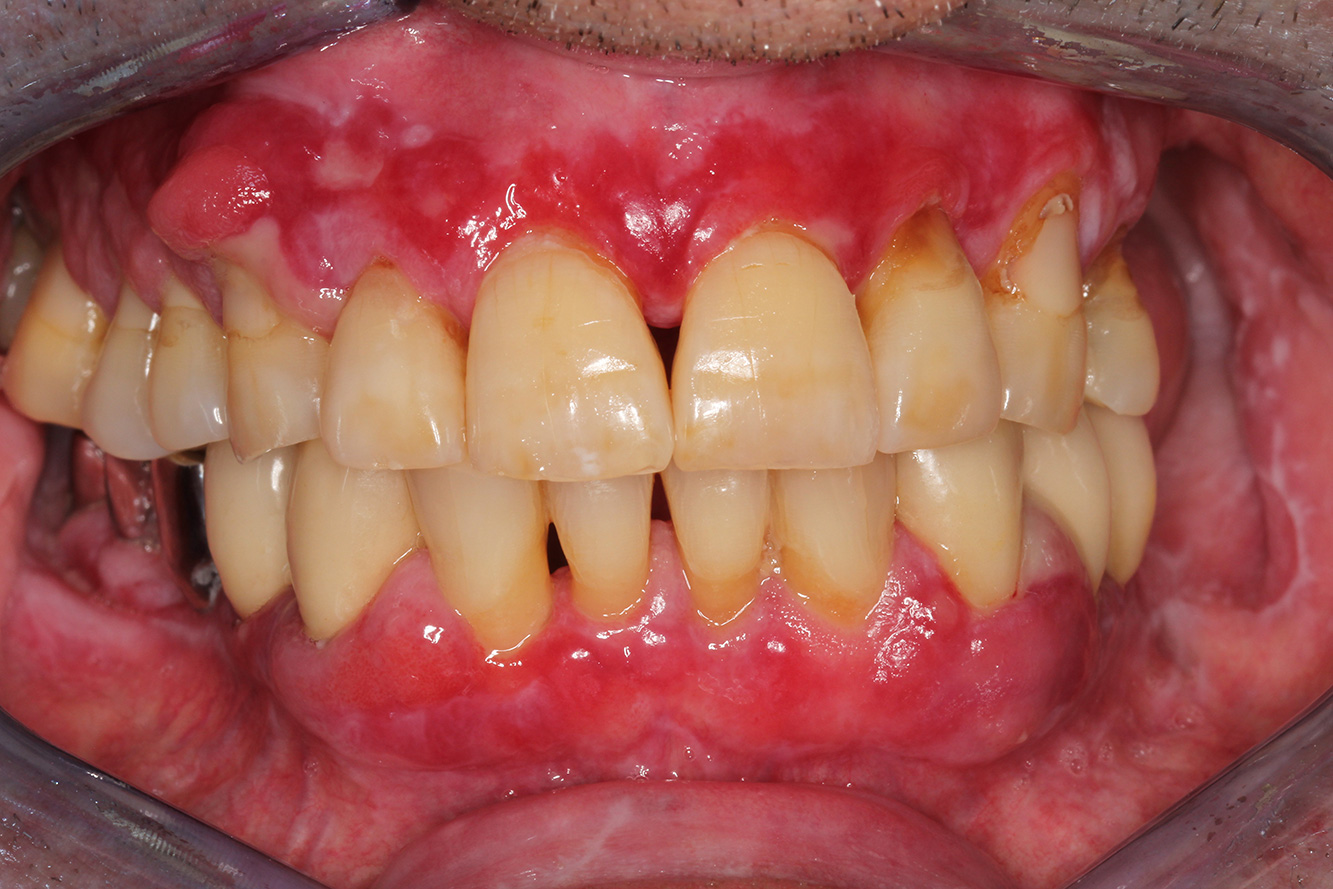

The Diabetic Patient with Pre-Existing Periodontitis

This case report of a 52-year-old male with type 2 diabetes and periodontitis emphasizes personalized preventive measures and periodontal health maintenance to manage the moderate disease progression risk. more